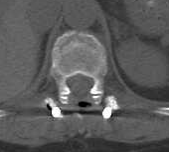

吴阿姨术前影像图

吴阿姨在干活时不慎从高处摔落,双脚当时就失去了知觉,无法活动,焦急万分的家人赶忙将她送往亚星手机版官方登录就医。脊柱病区的医生迅速为吴阿姨进行体格检查,结合胸腹部CT检查结果,初步诊断为胸腰椎骨折合并脊髓损伤、不全瘫痪。